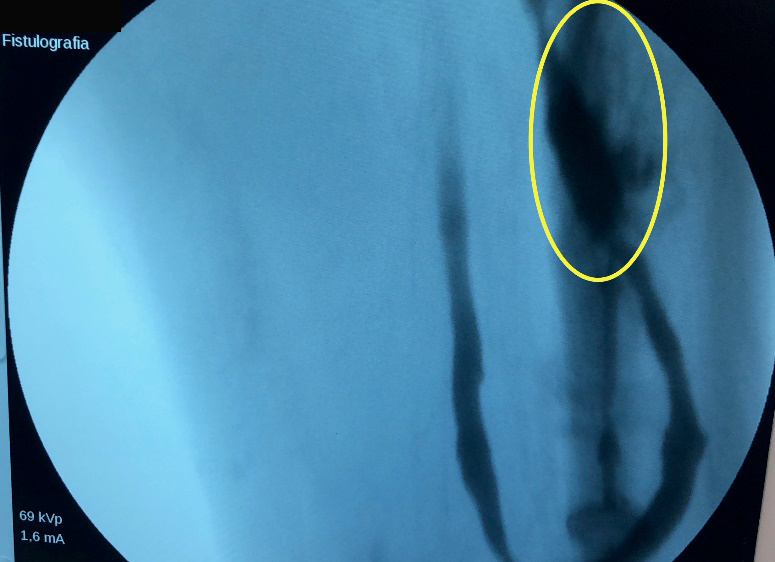

Se realizó ecodoppler, el cual informó permeabilidad del acceso vascular con aumento del espesor de la pared de la vena proximal a la arteria. Debido a la semiología, doppler y dinámica de la diálisis, se decidió ingresarla a quirófano a fin de realizar angiografía diagnóstica y, eventualmente, terapéutica. Durante el procedimiento se constató estenosis suboclusiva severa y extensa con repercusión hemodinámica, próxima a la anastomosis arterial, por lo que se decidió reparación endovascular con angioplastia con balón con droga de la FAV safeno-femoral en loop. (Imagen 3 . 4)

Se realizó una primera dilatación con balón simple de 5 x 60, durante 120 segundos continuos a 8 ATM. Control angiográfico: constató dilatación con pequeño flap de disección (Imagen 4). Se procedió a realizar angioplastía con balón con Paclitaxcel de 6 x 60 RANGER®, durante 180 segundos a 6 ATM, obteniendo resultado satisfactorio con buen flujo en el recorrido completo de todo el acceso sin necesidad de colocar stent.

Se obtuvo resultado satisfactorio con buen flujo en el recorrido completo de todo el acceso, mediante control angiográfico (Imagen 5 . 6).